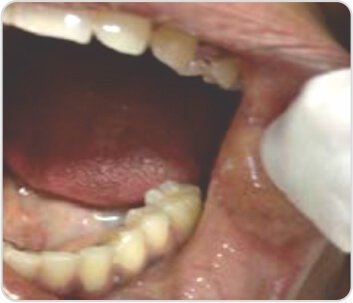

عند الفحص، كان المريض مستقرًا من الناحية الديناميكية الدموية بمعدل نبض قدره 90 في الدقيقة، وضغط دم يبلغ 140/90 ملم زئبق وتشبع بالأكسجين بنسبة 90٪ على مقياس التأكسج النبضي الذي يُمسك بالإصبع. أظهر فحص تجويف الفم توسع الشعيرات الدموية عن طريق الفم، وعند سماع الثدي الأيمن ومنطقة داخل الكتف اليمنى، تم سماع لغط خافت. كانت فحوصات البطن والعصبية طبيعية. وأظهرت التحقيقات أن الهيموجلوبين يبلغ 12.1 جم/ديسيلتر، وحجم الخلايا المعبأة 56%؛ عدد خلايا الدم البيضاء 9,400 لكل ملم مكعب (متعددة الأشكال 79%، خلايا ليمفاوية 17%، حمضات 2%، قاعدة 2%). وكانت المعلمات البيوكيميائية الأخرى ضمن الحدود الطبيعية. أظهر مخطط كهربية القلب (ECG) عدم انتظام دقات القلب الجيبي مع انحراف المحور الأيمن وموجة R في V1. نظرًا لأن المريض كان يعاني من عدة نوبات من الرعاف والاشتباه في حدوث انسداد رئوي، فقد خضع المريض لتصوير مقطعي محوسب للصدر وتصوير الأوعية الدموية الرئوية. كشف تصوير الأوعية الرئوية عن تمدد الأوعية الدموية الكاذب مع ناسور شرياني وريدي ناشئ عن فروع الشرايين الرئوية اليمنى.

توسع الشعريات عن طريق الفم